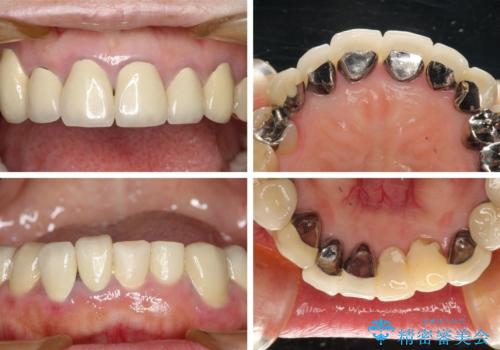

- 下顎の前歯に激痛を覚えて来院された患者様です。

取り急ぎ下顎前歯数歯の根管治療を、銀座しらゆり歯科医院長の林先生にお願いし、それ以外に気になっている、不自然な色調のクラウン、金属部分が見えてブラッシングがしにくいインプラント補綴、口元の突出感、出血のしやすい歯周ポケットなど、全てを解決するための治療を行うこととしました。

期間と費用はかかりましたが、気になっていた部分全てを改善でき、患者様には大変満足していただきました。